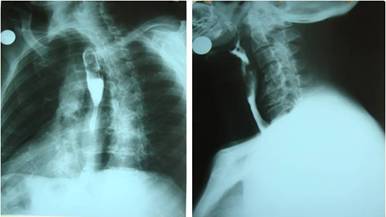

Esofagograma: El esófago cervical se encontraba opacificado en toda su extensión, con compresión extrínseca en su tercio distal por osteofitos anteriores de gran tamaño en las vértebras C4, C5, C6 y C7; también se observó estrechamiento anterior y posterior desde C4-C7 y esófago torácico opacificado totalmente con diámetro normal hasta su entrada en el estómago (Fig.2.).